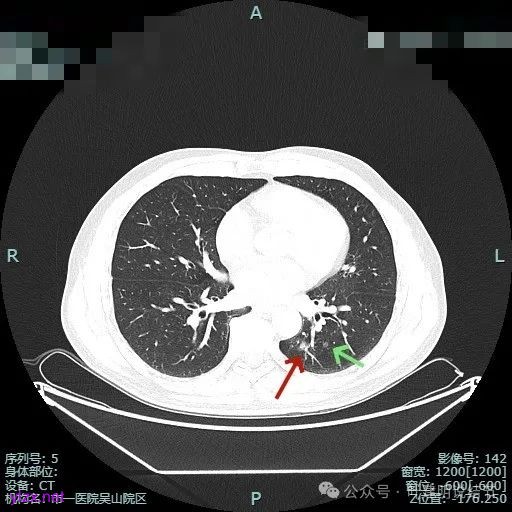

主病灶位于下叶后基底段下肺静脉水平,次病灶在同一层面位靠外基底段交界附近。

薄层上看主病灶不纯,有实性成分,也有血管穿行;次病灶是纯磨,微小的结节,但轮廓与边界较为清楚。

主病灶混合密度,血管进入;次病灶小且淡,但轮廓清。